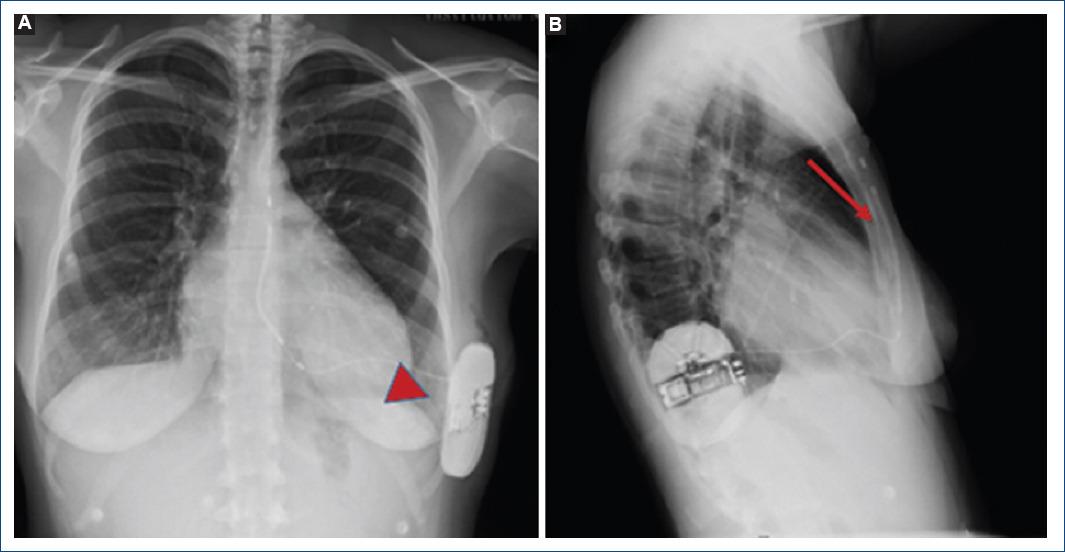

En la radiografía de tórax previa al alta (14/03/2018) se comprobó la normoposición del electrodo y el generador (Fig. 1). La paciente no ha tenido descargas en un seguimiento a cuatro años.

Figura 1 Radiografías de tórax en posición postero-anterior (A) y lateral (B) del primer desfibrilador automático implantable subcutáneo implantado en el Instituto Nacional de Cardiología Ignacio Chávez. Se observa el generador (cabeza de flecha) en adecuada posición al igual que el cable-electrodo (flecha).